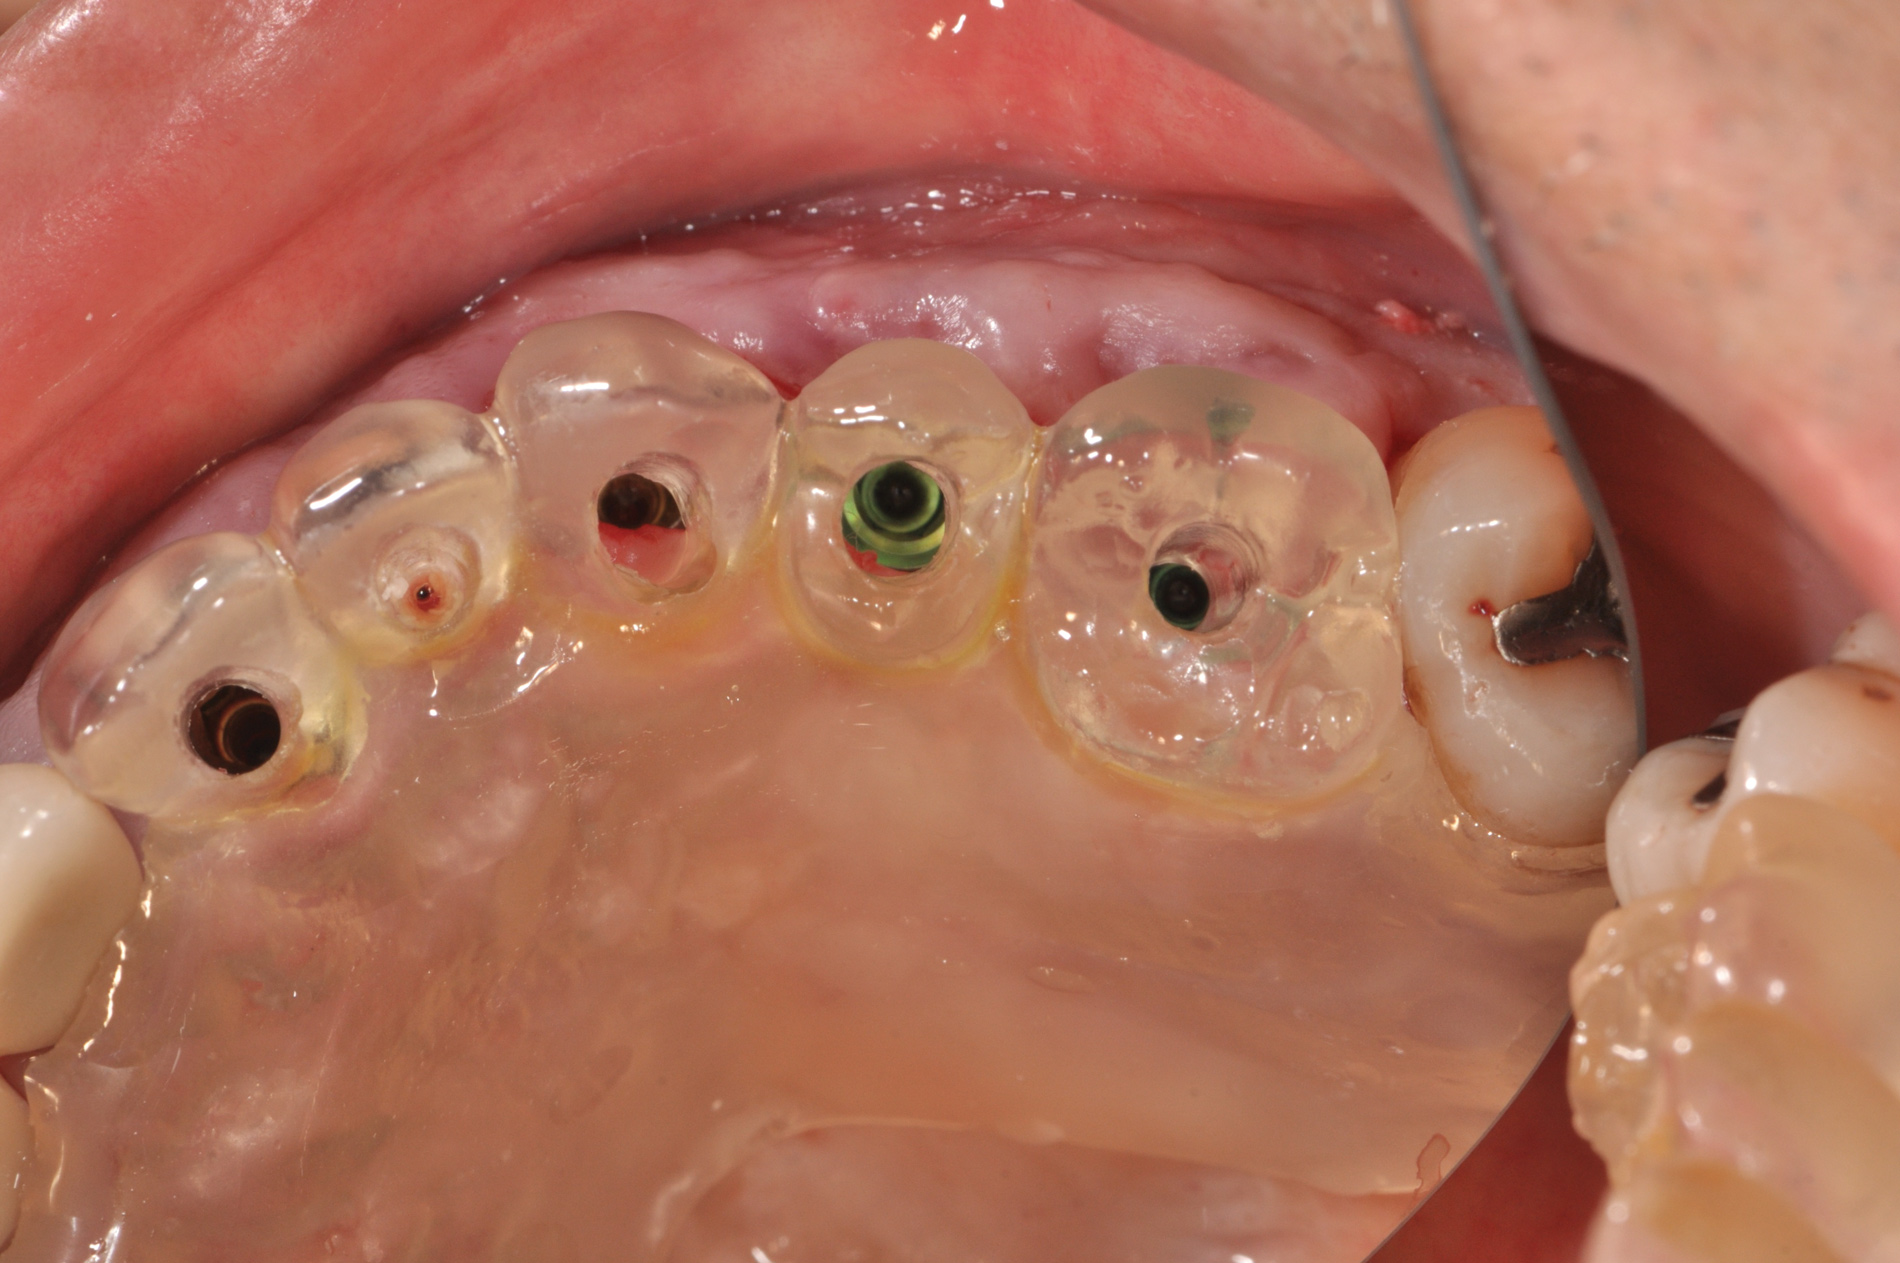

(25.) Preoperative view.

Figure 25

(26.) Guided-surgery template with inspection window.

Figure 26

(27.) Postoperative view of implants after 3-weeks of healing.

Figure 27

(28.) Postoperative periapical radiograph illustrating 2D implant positions.

Figure 28